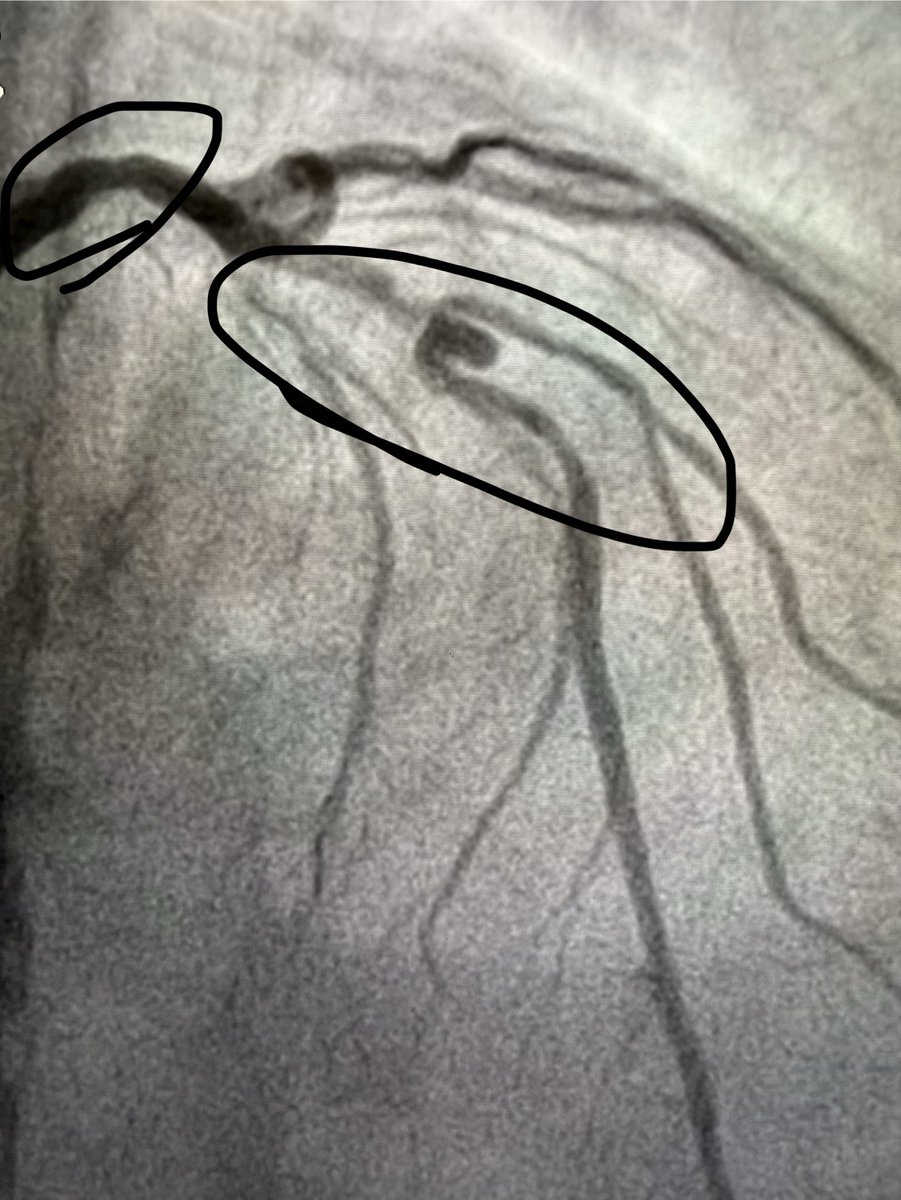

@AdityaMandawat DES across it and no change to DAPT duration. No anticoagulation for these smaller aneurysmal lesions